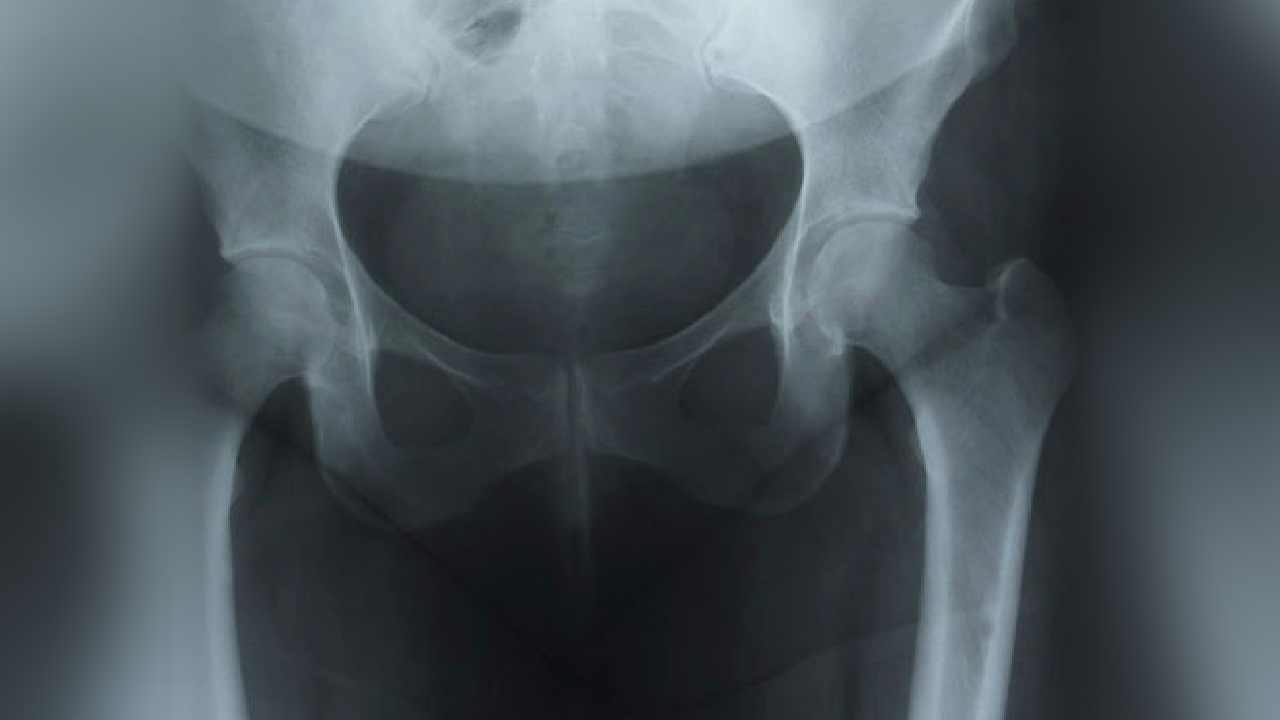

As you get older, your bones may get weaker. This is called "osteoporosis." Weak bones are more likely to break. Osteoporosis can be a problem for anyone, but it is more common in women.

Your body is always rebuilding your bones. When bone cells get old, they break down and get replaced. But as you age, your body can't keep up. Old bone breaks down faster than it can be replaced. Your bones gradually lose some of their strength. If they get too weak, you are said to have osteoporosis.

Osteoporosis can cause your back to hurt. Your back may begin to curve forward. You may get shorter. And you may break a bone easily, even by coughing or bending over.